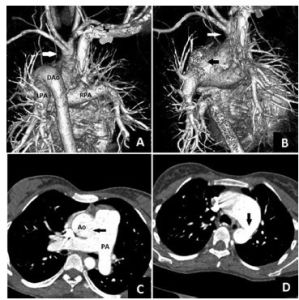

主動脈肺動脈窗是位於主動脈升部與主動脈胸部之間的一個身體部位,包括動脈韌帶、動脈韌帶淋巴結。CT圖像是低密度空隙。

主動脈肺動脈窗-肺動脈窗是半月瓣以上升主動脈和肺動脈之間的異常交通,是一種罕見的先天性...留有殘缺,形成此病。主-肺動脈窗多位於升主動脈左後外壁或其後壁,與相鄰...與肺動脈相續。術中須避免造成右肺動脈或升主動脈狹窄。(3)主-肺動脈窗合併...

發病原因 疾病概述 症狀體徵 病理生理 診斷檢查、主動脈和肺動脈等的情況得出全面的印象,並可觀察胸部有無其他異常改變,從而作出...動脈、主動脈弓上緣與脊椎前緣構成;弓下有主動脈窗,其中包括有氣管分叉、左主支氣管和左肺動脈。主動脈降部見於心影后方,部分與脊椎重疊。 記波攝影...